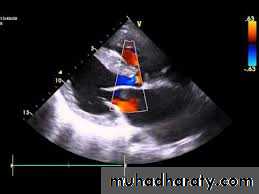

Echocardiography.

Two-dimensional and Doppler echo studies can identify the number, size, and exact location of the defect; estimate PA pressure; identify other associated defects; and estimate the magnitude of the shunt.NATURAL HISTORY